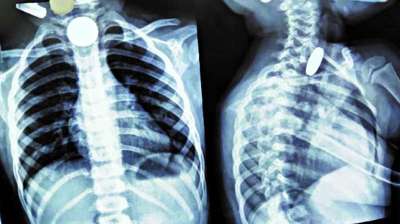

खिलौना नहीं सिक्का था! बच्चे ने निगले 5-10 रुपये के सिक्के, डॉक्टरों ने ऑपरेशन कर निकाले

24 Jul, 2025 04:09 PM IST | PARWAZTIMES.COM

दिल्ली : दिल्ली के एक सरकारी अस्पताल के डॉक्टरों ने 12 वर्षीय बच्चे की जान बचाई है। बच्चे ने पांच और दस रुपये के तीन सिक्के निगल लिए थे। सिक्के...